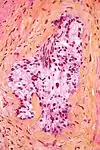

Micrograph of a HPS stained section demonstrating perineural spread of prostate adenocarcinoma.

In histology, the HPS stain, or hematoxylin phloxine saffron stain, is a way of marking tissues.

HPS is similar to H&E, the standard bearer in histology. However, it differentiates between the most common connective tissue (collagen) and muscle and cytoplasm by staining the former yellow and the latter two pink,[1] unlike an H&E stain, which stains all three pink.